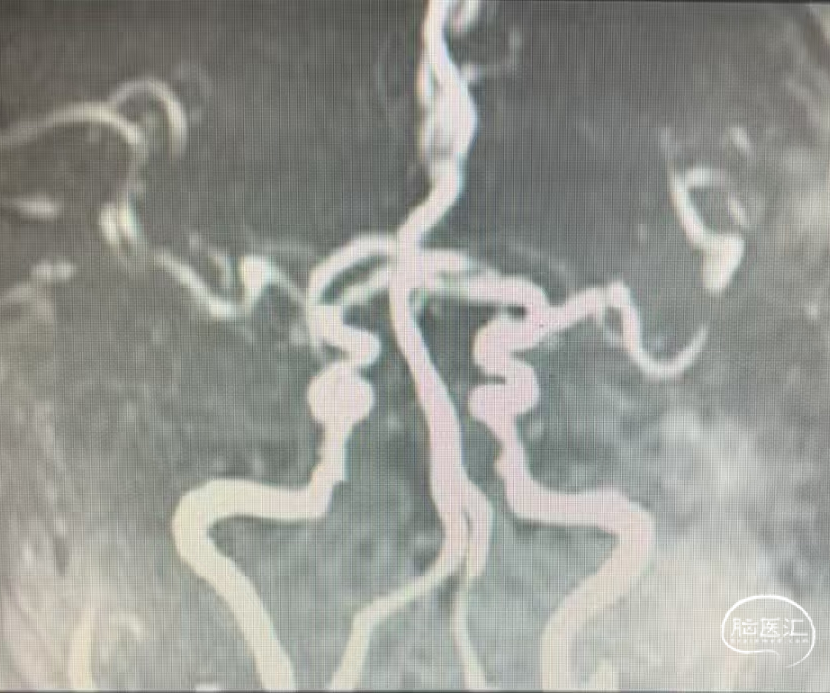

术前MRA:右侧大脑中动脉闭塞。

评估病变及代偿:Ⅰ型弓,右侧大脑中动脉闭塞,软脑膜动脉、大脑前动脉对其部分代偿,ASITN/SIR 2级。